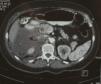

La tomografía axial computada reveló marcada dilatación de la vía biliar intra- y extrahepática, sin lograr identificar la vesícula biliar; además, se observó la presencia de líquido en el área pararrenal anterior y posterior (figs. 1–3).